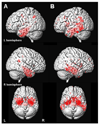

Main outcome measure: Patterns of gray matter loss in the MCI groups compared with control subjects, assessed using voxel-based morphometry.

Results: Subjects in the amnestic single- and multiple-domain groups showed loss in the medial and inferior temporal lobes compared with control subjects, and those in the multiple-domain group also had involvement of the posterior temporal lobe, parietal association cortex, and posterior cingulate. Subjects in the nonamnestic single-domain group with language impairment showed loss in the left anterior inferior temporal lobe. The group with attention/executive deficits showed loss in the basal forebrain and hypothalamus. No coherent patterns of loss were observed in the other subgroups.